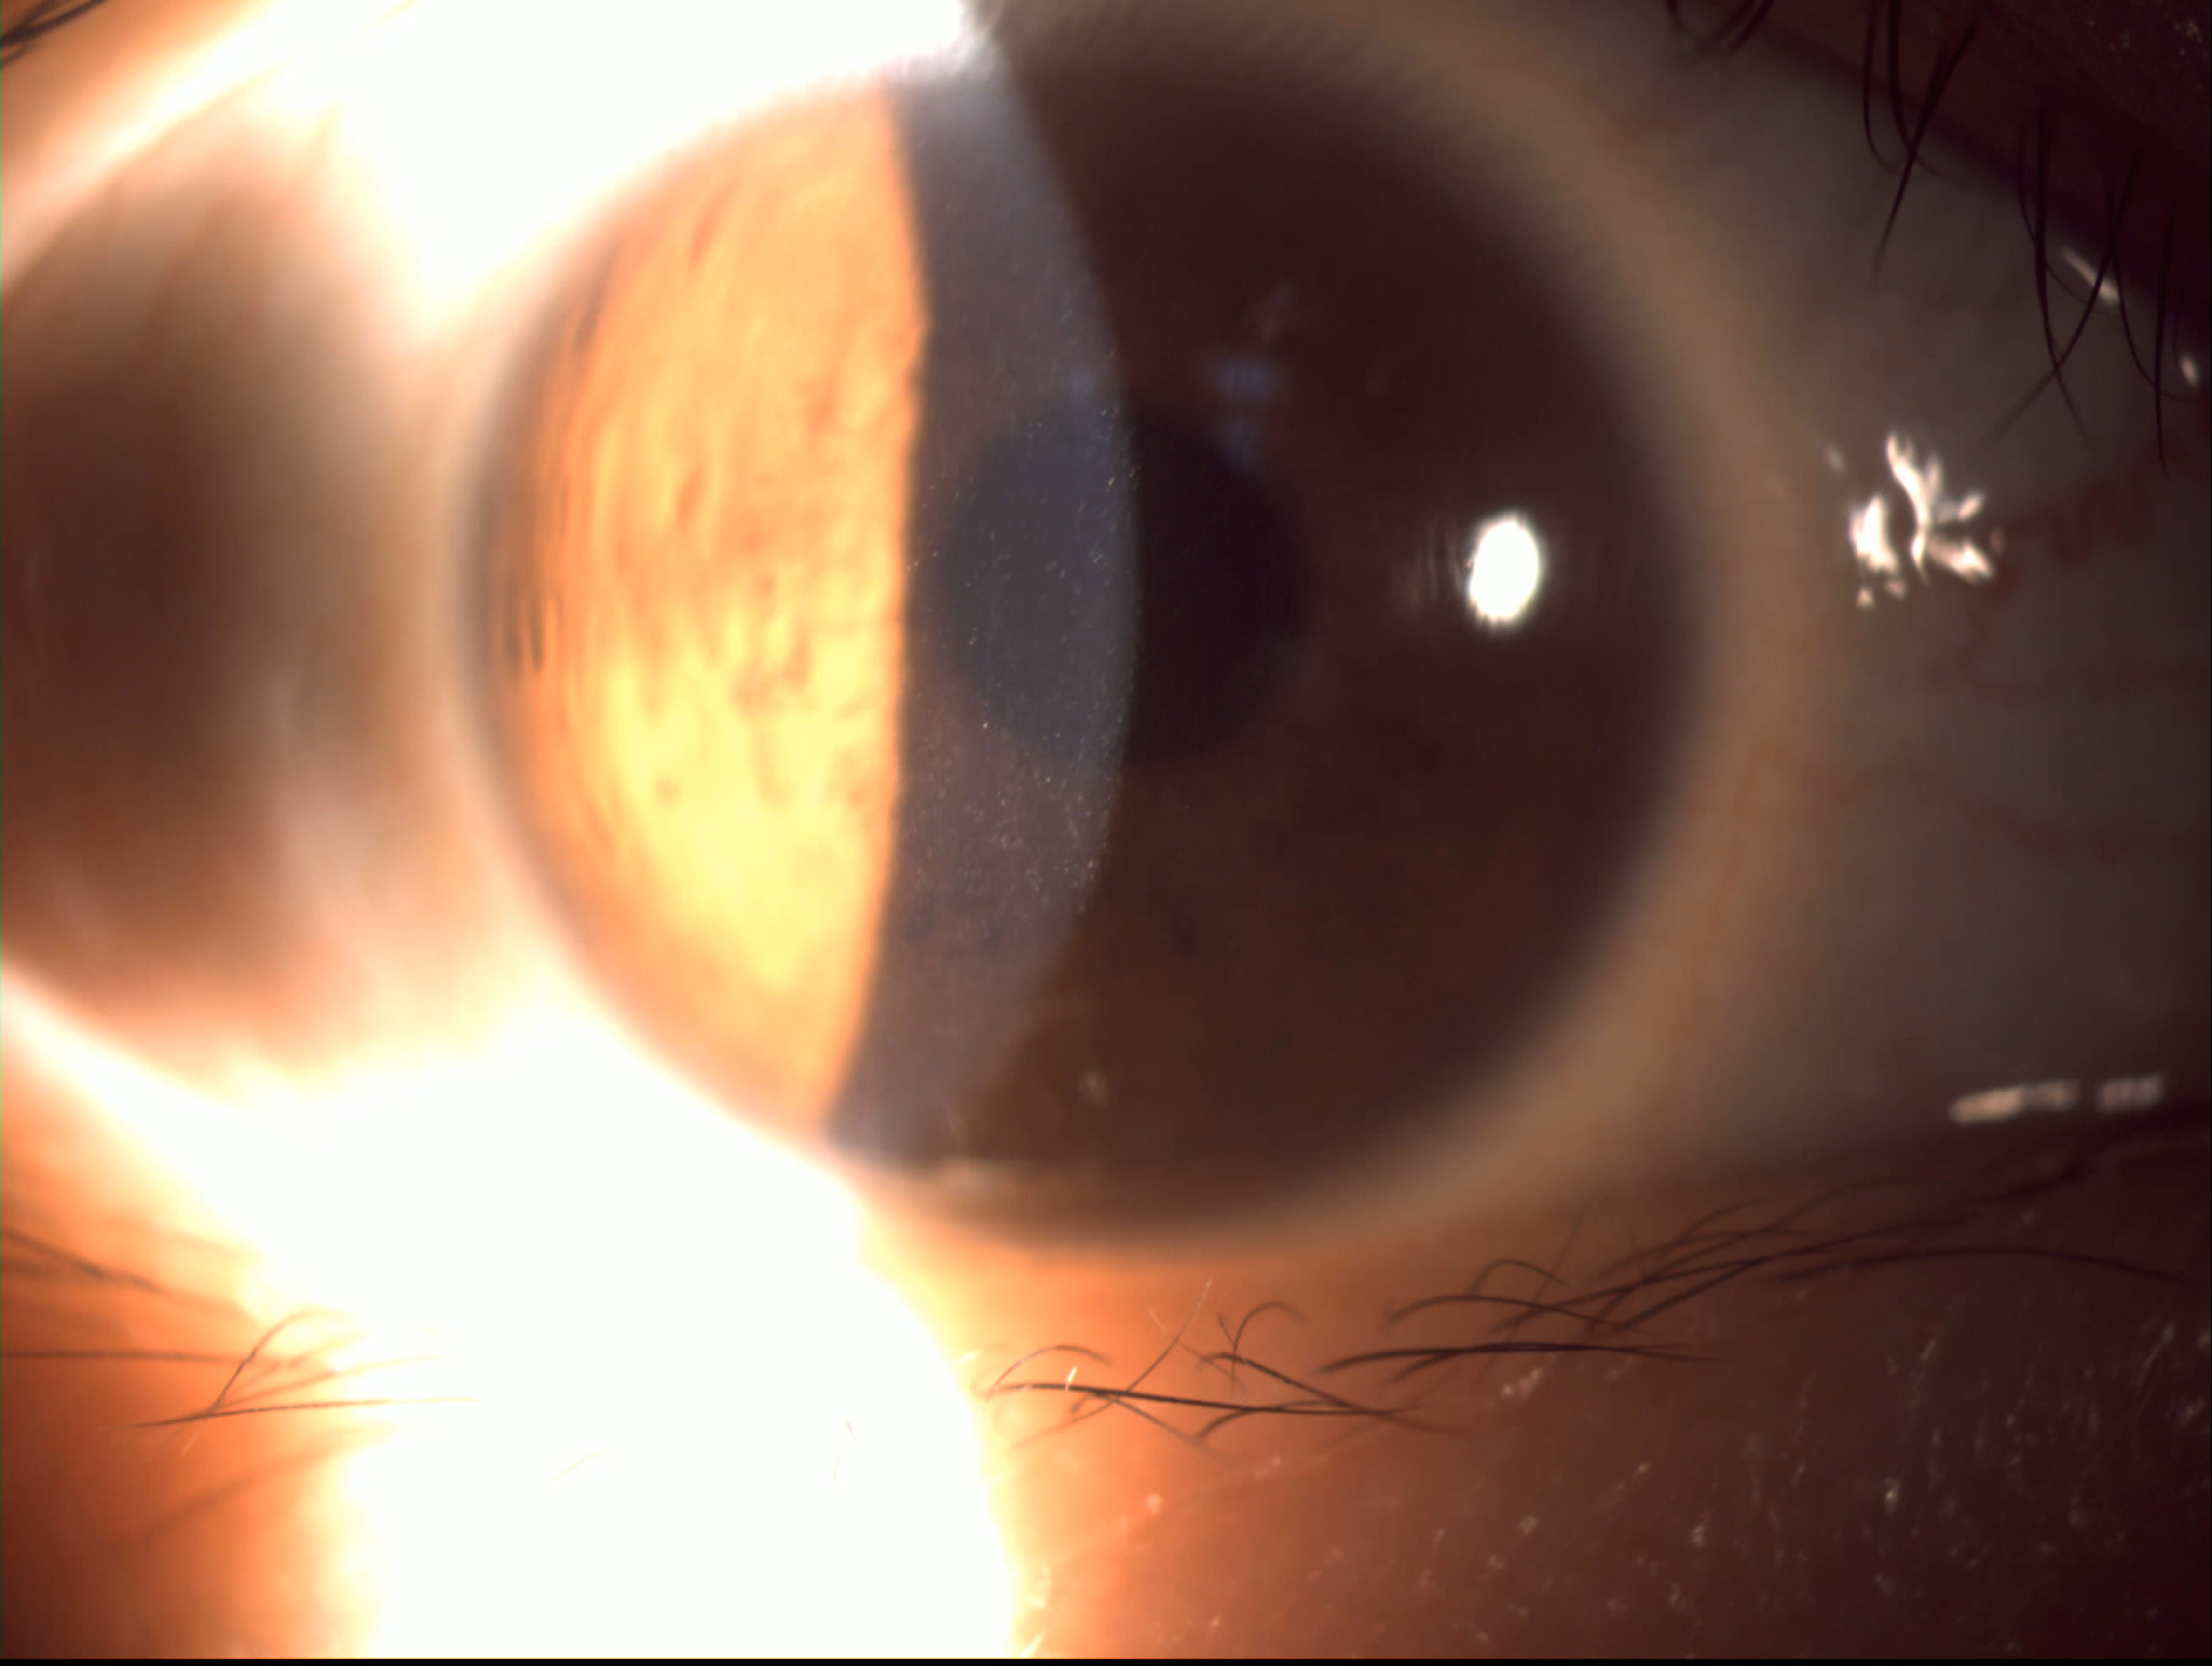

在看裂隙灯就发现问题了。

上图为右眼

上图为左眼